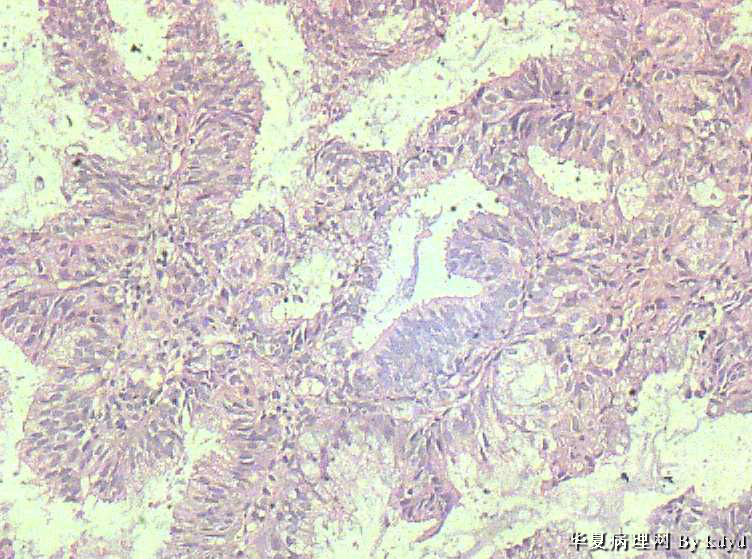

51岁,停经一年后,阴道流血。行宫腔诊刮。

B超示:宫腔有一赘生物大小1.5*2.5大小。

肉眼观:少许粘液及碎组织。(全包)

疑问:1。腺体呈复杂性增生伴不典型增生?

2。腺体有分泌反应,有些腺体看上去又像是宫颈的腺体(手术医生说是宫腔取的)?

3。怎样报告???

• 腺体非典型增生?是宫腔还是宫颈??图1

• 腺体非典型增生?是宫腔还是宫颈??图2

图2

• 腺体非典型增生?是宫腔还是宫颈??图3

图3

• 腺体非典型增生?是宫腔还是宫颈??图4

图4

腺体密集,有背靠背、共壁,有乳头状结构,有核异性性,有病理核分裂:

子宫内膜中-重度不典型增生,癌变不能排除

宫内膜样癌(高分化)。组织腺体拥挤、背靠背、血管纤维轴心乳头状,间质细胞消失代之纤维。